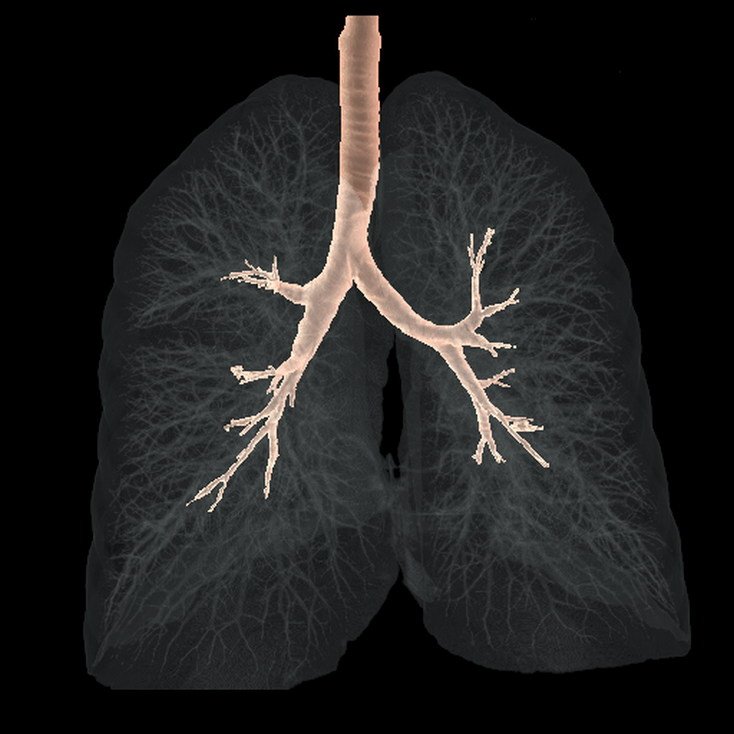

3D CT lung

3D CT Trachea & Bronchus

CT Lung

Virtual Bronchoscopy